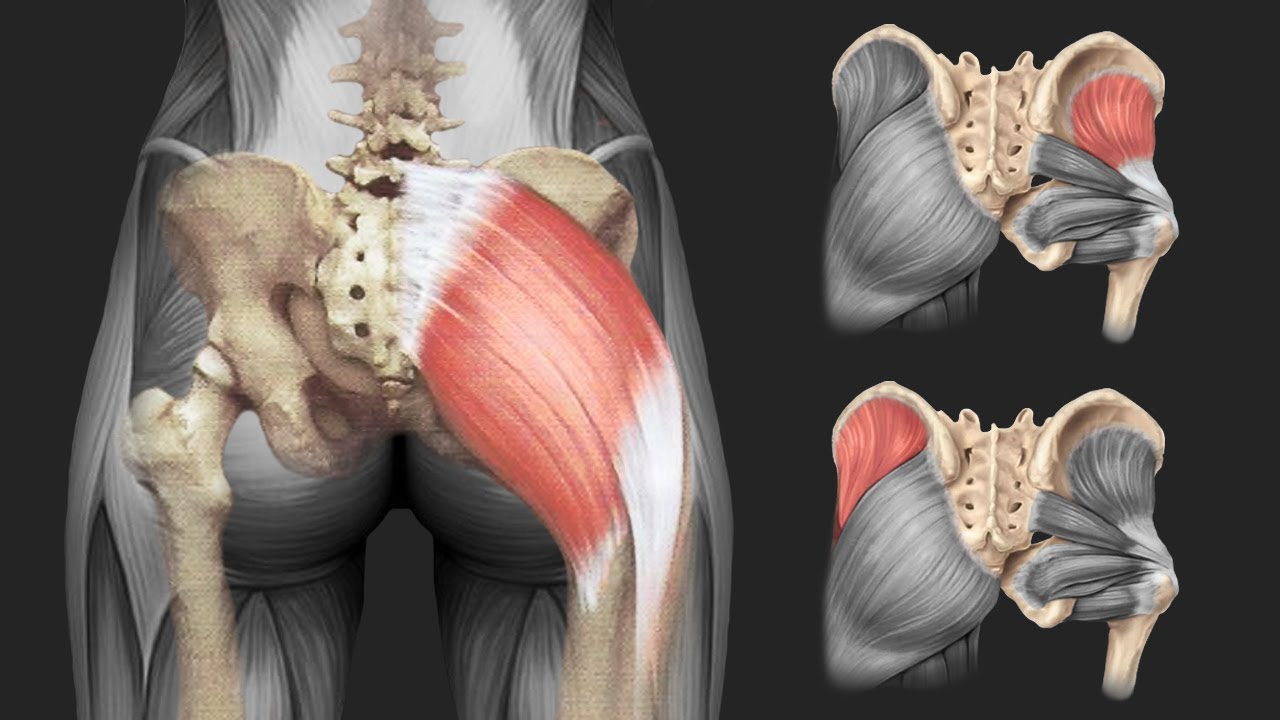

The Impact of Muscle Tissue on Fracture Healing

The relationship between muscle tissue and bone healing has been a subject of increasing interest in recent years. How do muscles influence fracture repair?

Muscles contribute to fracture healing through various mechanisms:

- Providing a rich source of blood supply to the fracture site

- Secreting growth factors and cytokines that promote bone formation

- Offering mechanical stimulation that enhances bone regeneration

- Serving as a potential source of osteoprogenitor cells

Studies have shown that muscle flap coverage can significantly improve bone blood flow and enhance the strength of union at fracture sites, particularly in cases of devascularized bone segments.

Muscle Flaps in Clinical Practice

The use of muscle flaps in the treatment of complex fractures and non-unions has gained popularity in recent years. Clinical studies have demonstrated improved outcomes in cases where muscle flap coverage was employed, particularly in the management of open fractures and infected non-unions.